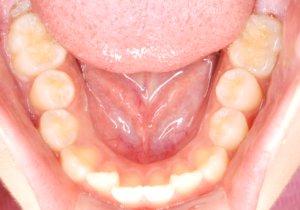

施術前

| 治療内容 | 第一大臼歯の裂溝が深いため、シーラントをし予防処置を行った。 |

| 治療のリスク | 脱離がないか、経過観察を行う必要がある。 |